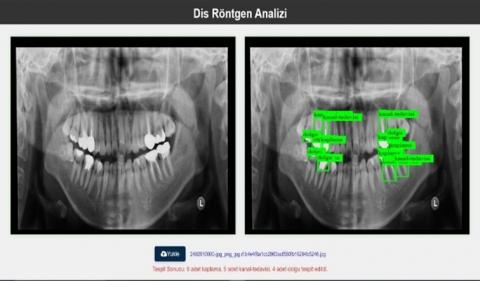

The trained model was made accessible through a user-friendly web interface. This is intended to significantly increase the speed and accessibility of the process. The web interface is designed in such a way that dentists and students can easily use it, and users can access the analysis results quickly and reliably by directly uploading dental X-ray images. As can be seen in Figure 6, the detected diseases or previously applied procedures can be instantly displayed on the uploaded images. In this way, faster transition to treatment processes is ensured and future complications can be prevented by early diagnosis in many diseases. The web interface has been designed in a user-friendly structure to help rapid decision-making in clinical settings and to increase the suitability of the model for practical use.

Figure 6. Web interface

As can be seen in Figure 6, it is possible to determine which disease is present in the dental X-ray whose image is uploaded or which procedures have been performed on this tooth structure before. Thus, it is aimed to provide a faster transition to the treatment process. It is thought that early diagnosis and treatment of many diseases can prevent future problems.